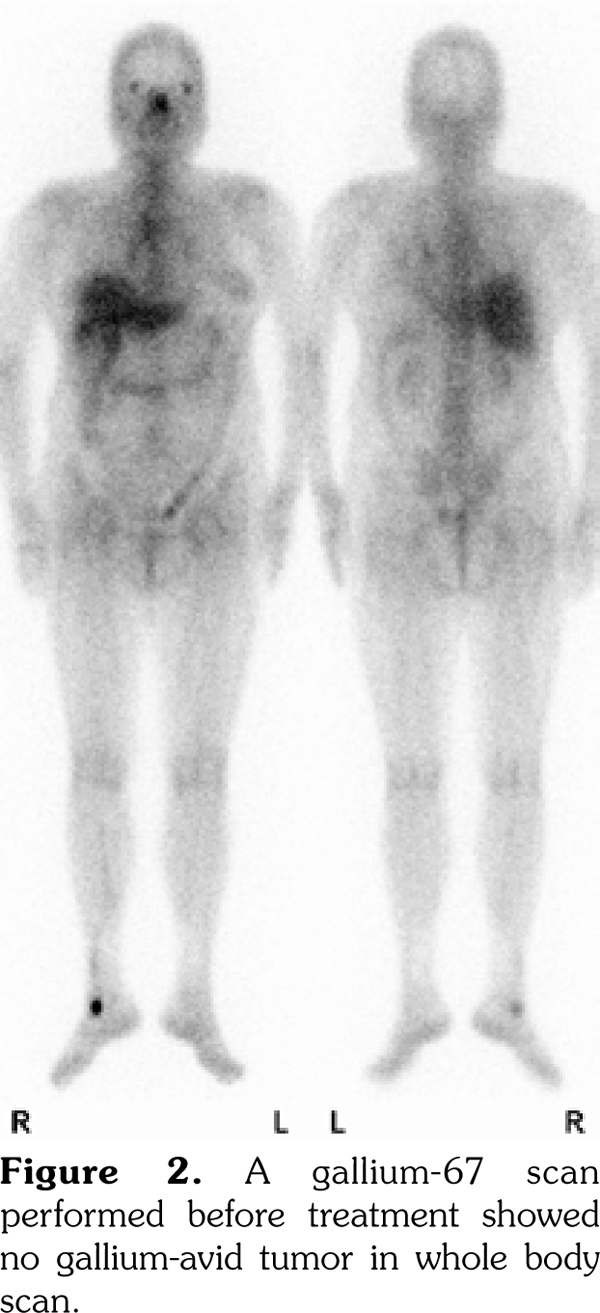

In this case, we were unable to diagnose bone marrow involvement since no bone marrow biopsy was performed. There was mild and diffuse increase of FDG uptake in the bone marrow with a maximum standard uptake value of 2.5 in the spines, which was similar to the FDG uptake in the liver. According to a study by Inoue et al.,(14) a bone marrow F-18 FDG uptake greater than or equal to that of the liver may indicate bone marrow hyperactivity. Therefore, bone marrow involvement could not be ruled out in this case. The PET/CT six months later revealed that the maximum standard uptake value decreased to 2.0 in the spines and was less than that in the liver (Figure 3).